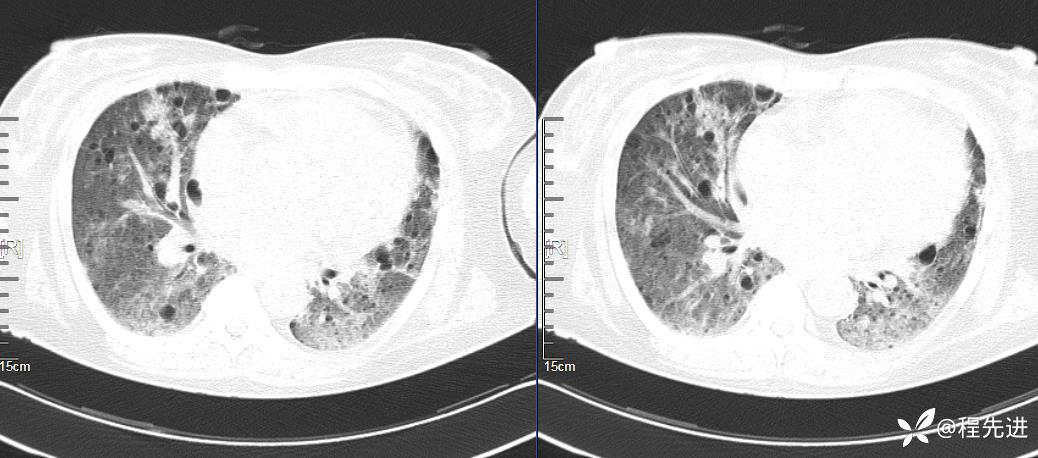

CT平扫(纵隔窗无特殊,就不上传了):

2、本例肺气囊分布有什么特点?肺气囊有无小叶核心?有没有间质纤维化及伴发结节?